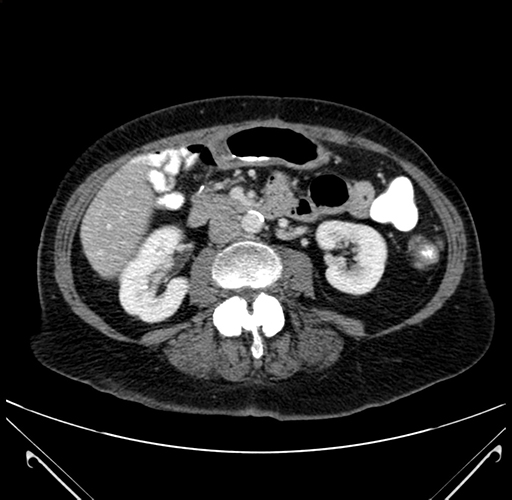

Pre-Chemo: Axial Venous

Axial Venous